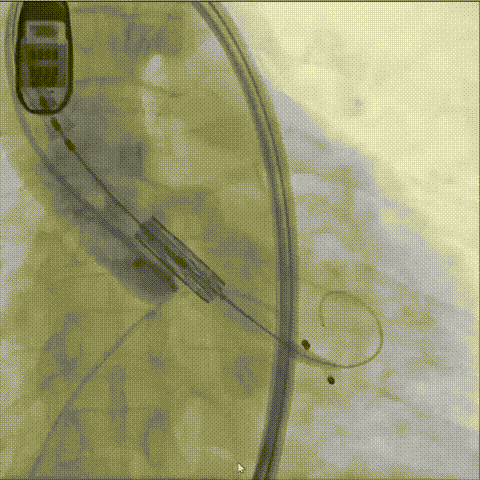

瓣膜释放

球囊预扩